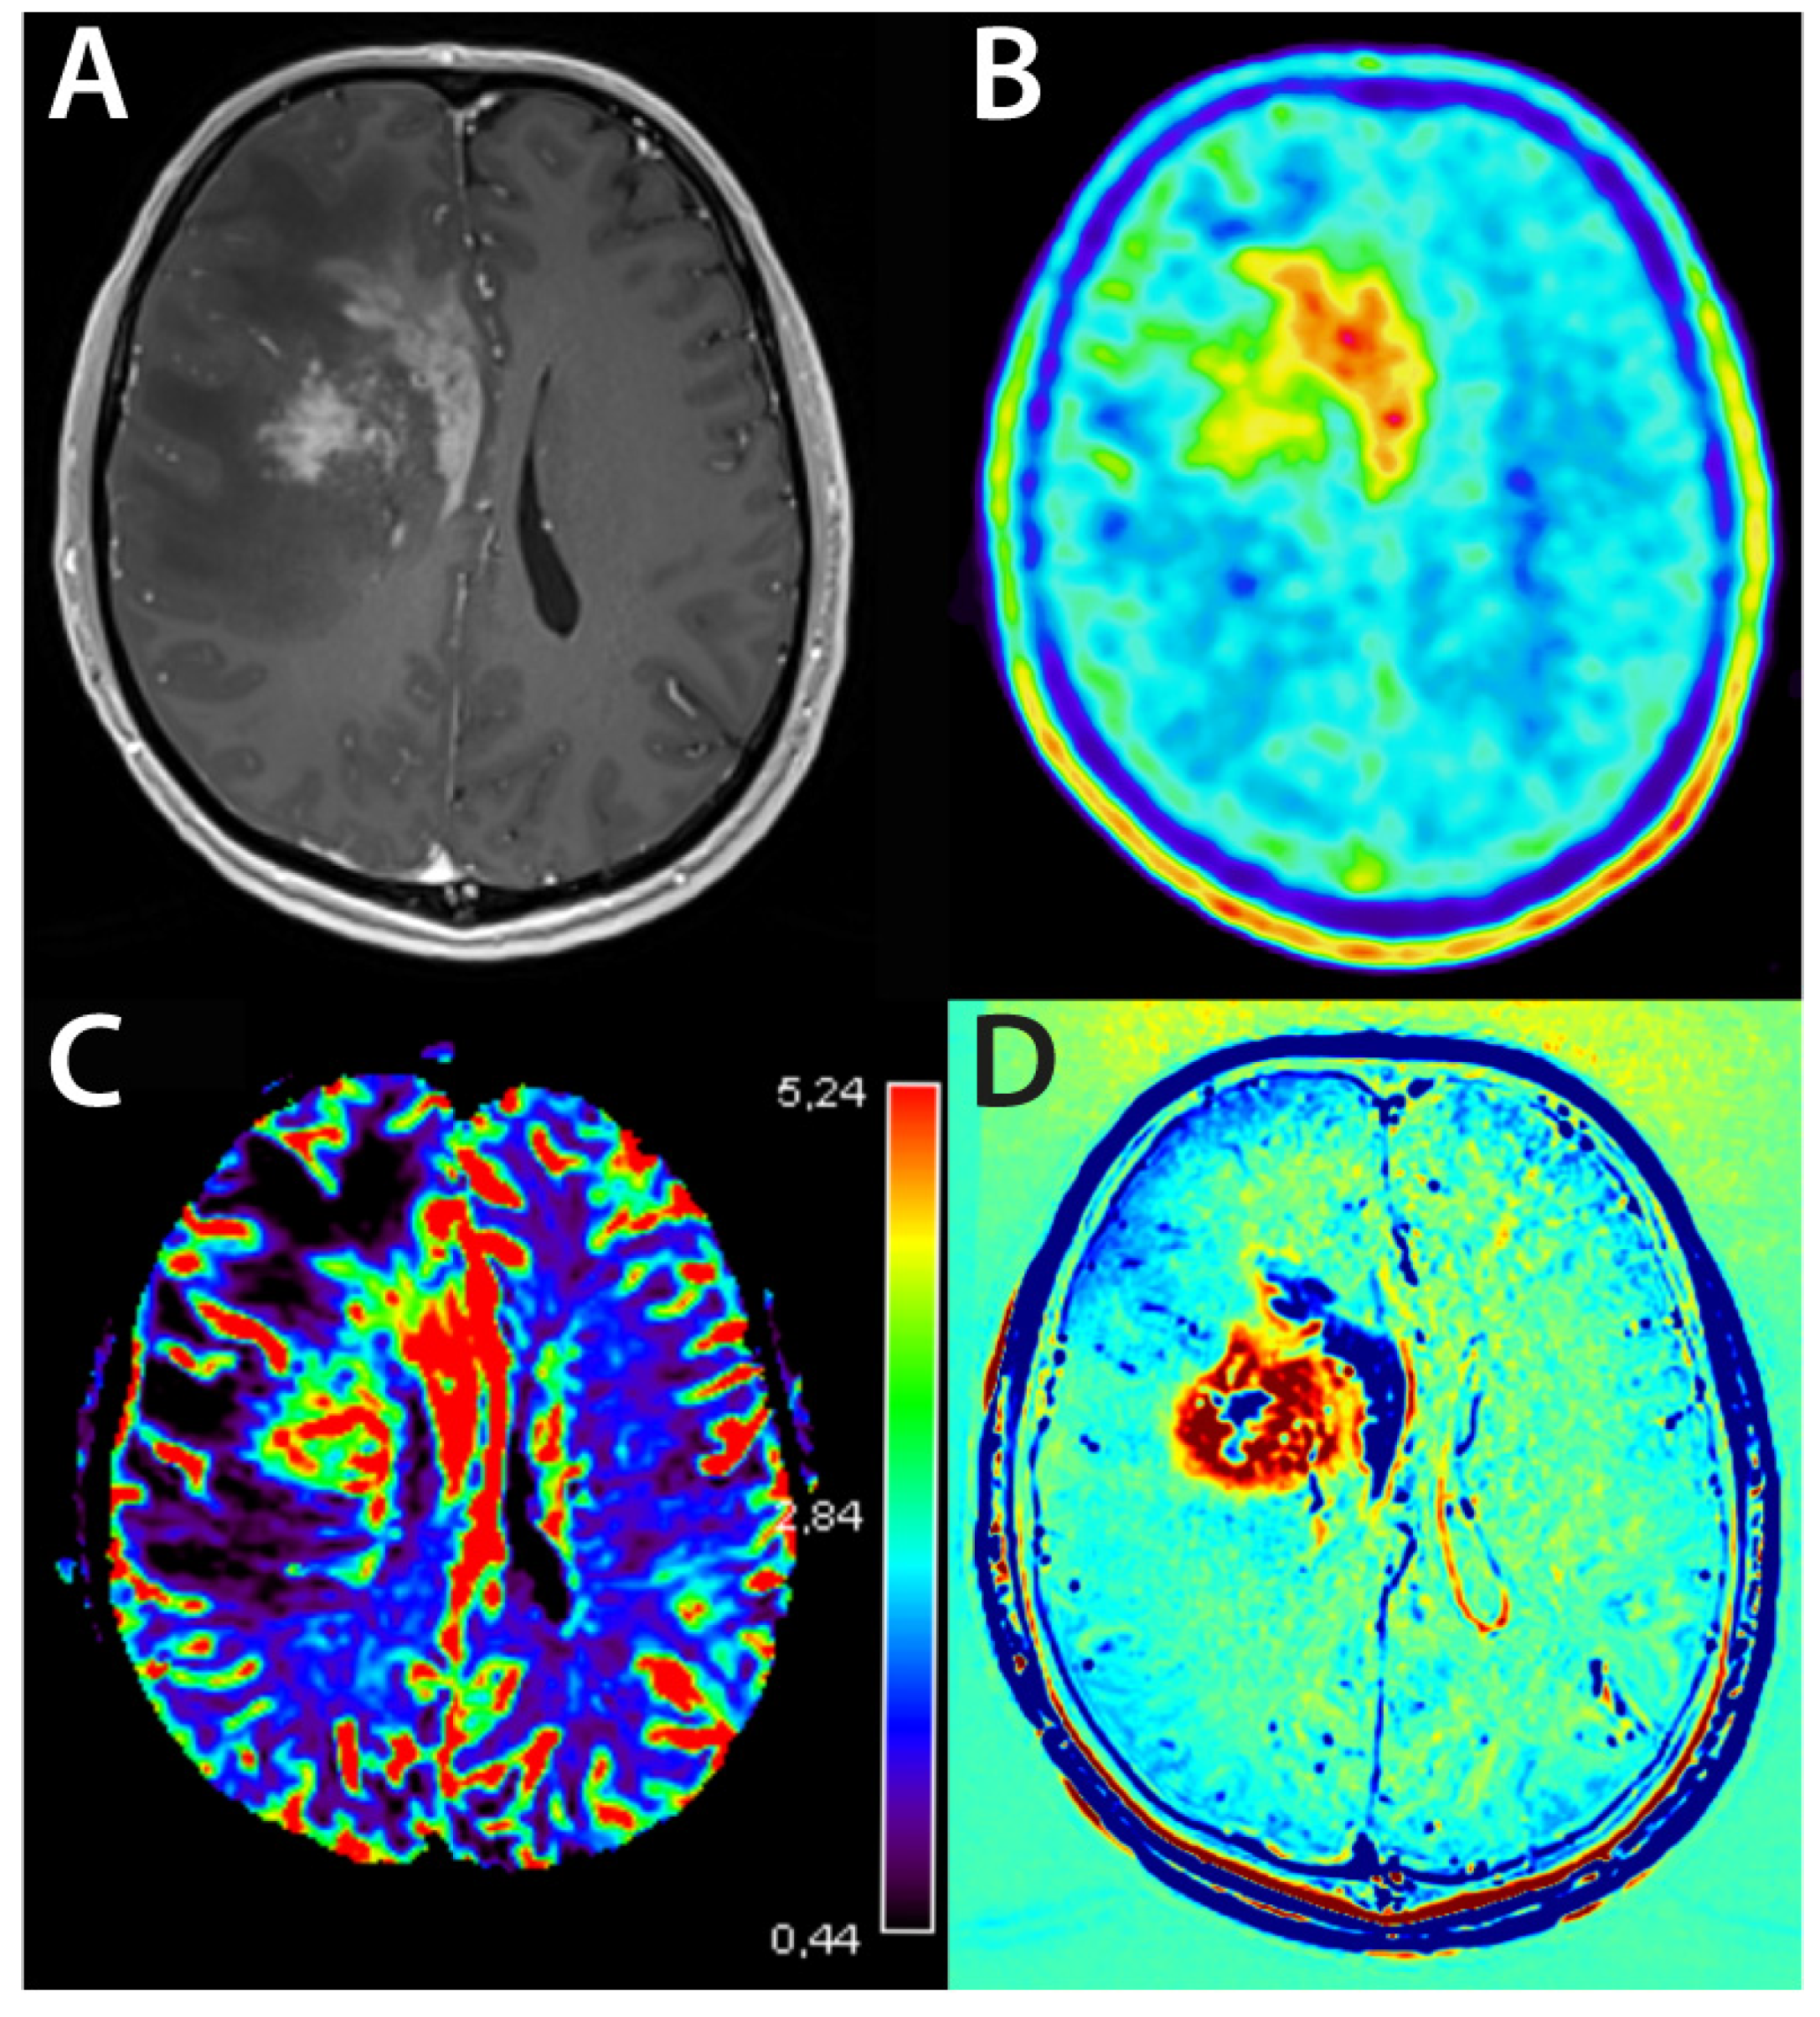

4.1.4. Perfusion-Weighted Imaging—Glioma

4.1.5. Perfusion-Weighted Imaging—Metastases

4.2.1. Delayed Contrast Extravasation MRI and Quantitative Imaging

- Mitsuya, K.; Nakasu, Y.; Horiguchi, S.; Harada, H.; Nishimura, T.; Bando, E.; Okawa, H.; Furukawa, Y.; Hirai, T.; Endo, M. Perfusion Weighted Magnetic Resonance Imaging to Distinguish the Recurrence of Metastatic Brain Tumors from Radiation Necrosis after Stereotactic Radiosurgery. J. Neurooncol. 2010, 99, 81–88. [Google Scholar] [CrossRef]

- Barajas, R.F.; Chang, J.S.; Sneed, P.K.; Segal, M.R.; McDermott, M.W.; Cha, S. Distinguishing Recurrent Intra-Axial Metastatic Tumor from Radiation Necrosis Following Gamma Knife Radiosurgery Using Dynamic Susceptibility-Weighted Contrast-Enhanced Perfusion Mr Imaging. AJNR Am. J. Neuroradiol. 2009, 30, 367–372. [Google Scholar] [CrossRef] [PubMed]

- Barajas, R.F., Jr.; Chang, J.S.; Segal, M.R.; Parsa, A.T.; McDermott, M.W.; Berger, M.S.; Cha, S. Differentiation of Recurrent Glioblastoma Multiforme from Radiation Necrosis after External Beam Radiation Therapy with Dynamic Susceptibility-Weighted Contrast-Enhanced Perfusion Mr Imaging. Radiology 2009, 253, 486–496. [Google Scholar] [CrossRef]